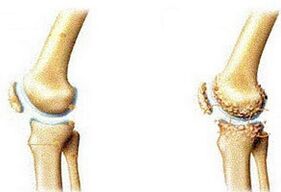

A artrose é uma doença associada a alterações relacionadas à idade na estrutura da cartilagem articular. Geralmente se desenvolve após 45 anos. Se a artrite das articulações é de natureza inflamatória, então a artrose é entendida como a destruição gradual do tecido cartilaginoso.

Normalmente, a cartilagem articular é elástica e resiliente. Ao se movimentar, é liberado o chamado líquido sinovial, que atua como lubrificante natural. Mas com a idade, a cartilagem fica mais fina, perdendo força e elasticidade. Com o tempo, aparecem sulcos, protuberâncias e depósitos de sal, que interferem na livre movimentação.

- Gonartrose – artrose do joelho. Muito comum e mais comum em mulheres. Os osteófitos geralmente aparecem na cartilagem afetada - espinhos ou crescimentos que surgem como resultado de alterações na estrutura do tecido ósseo;